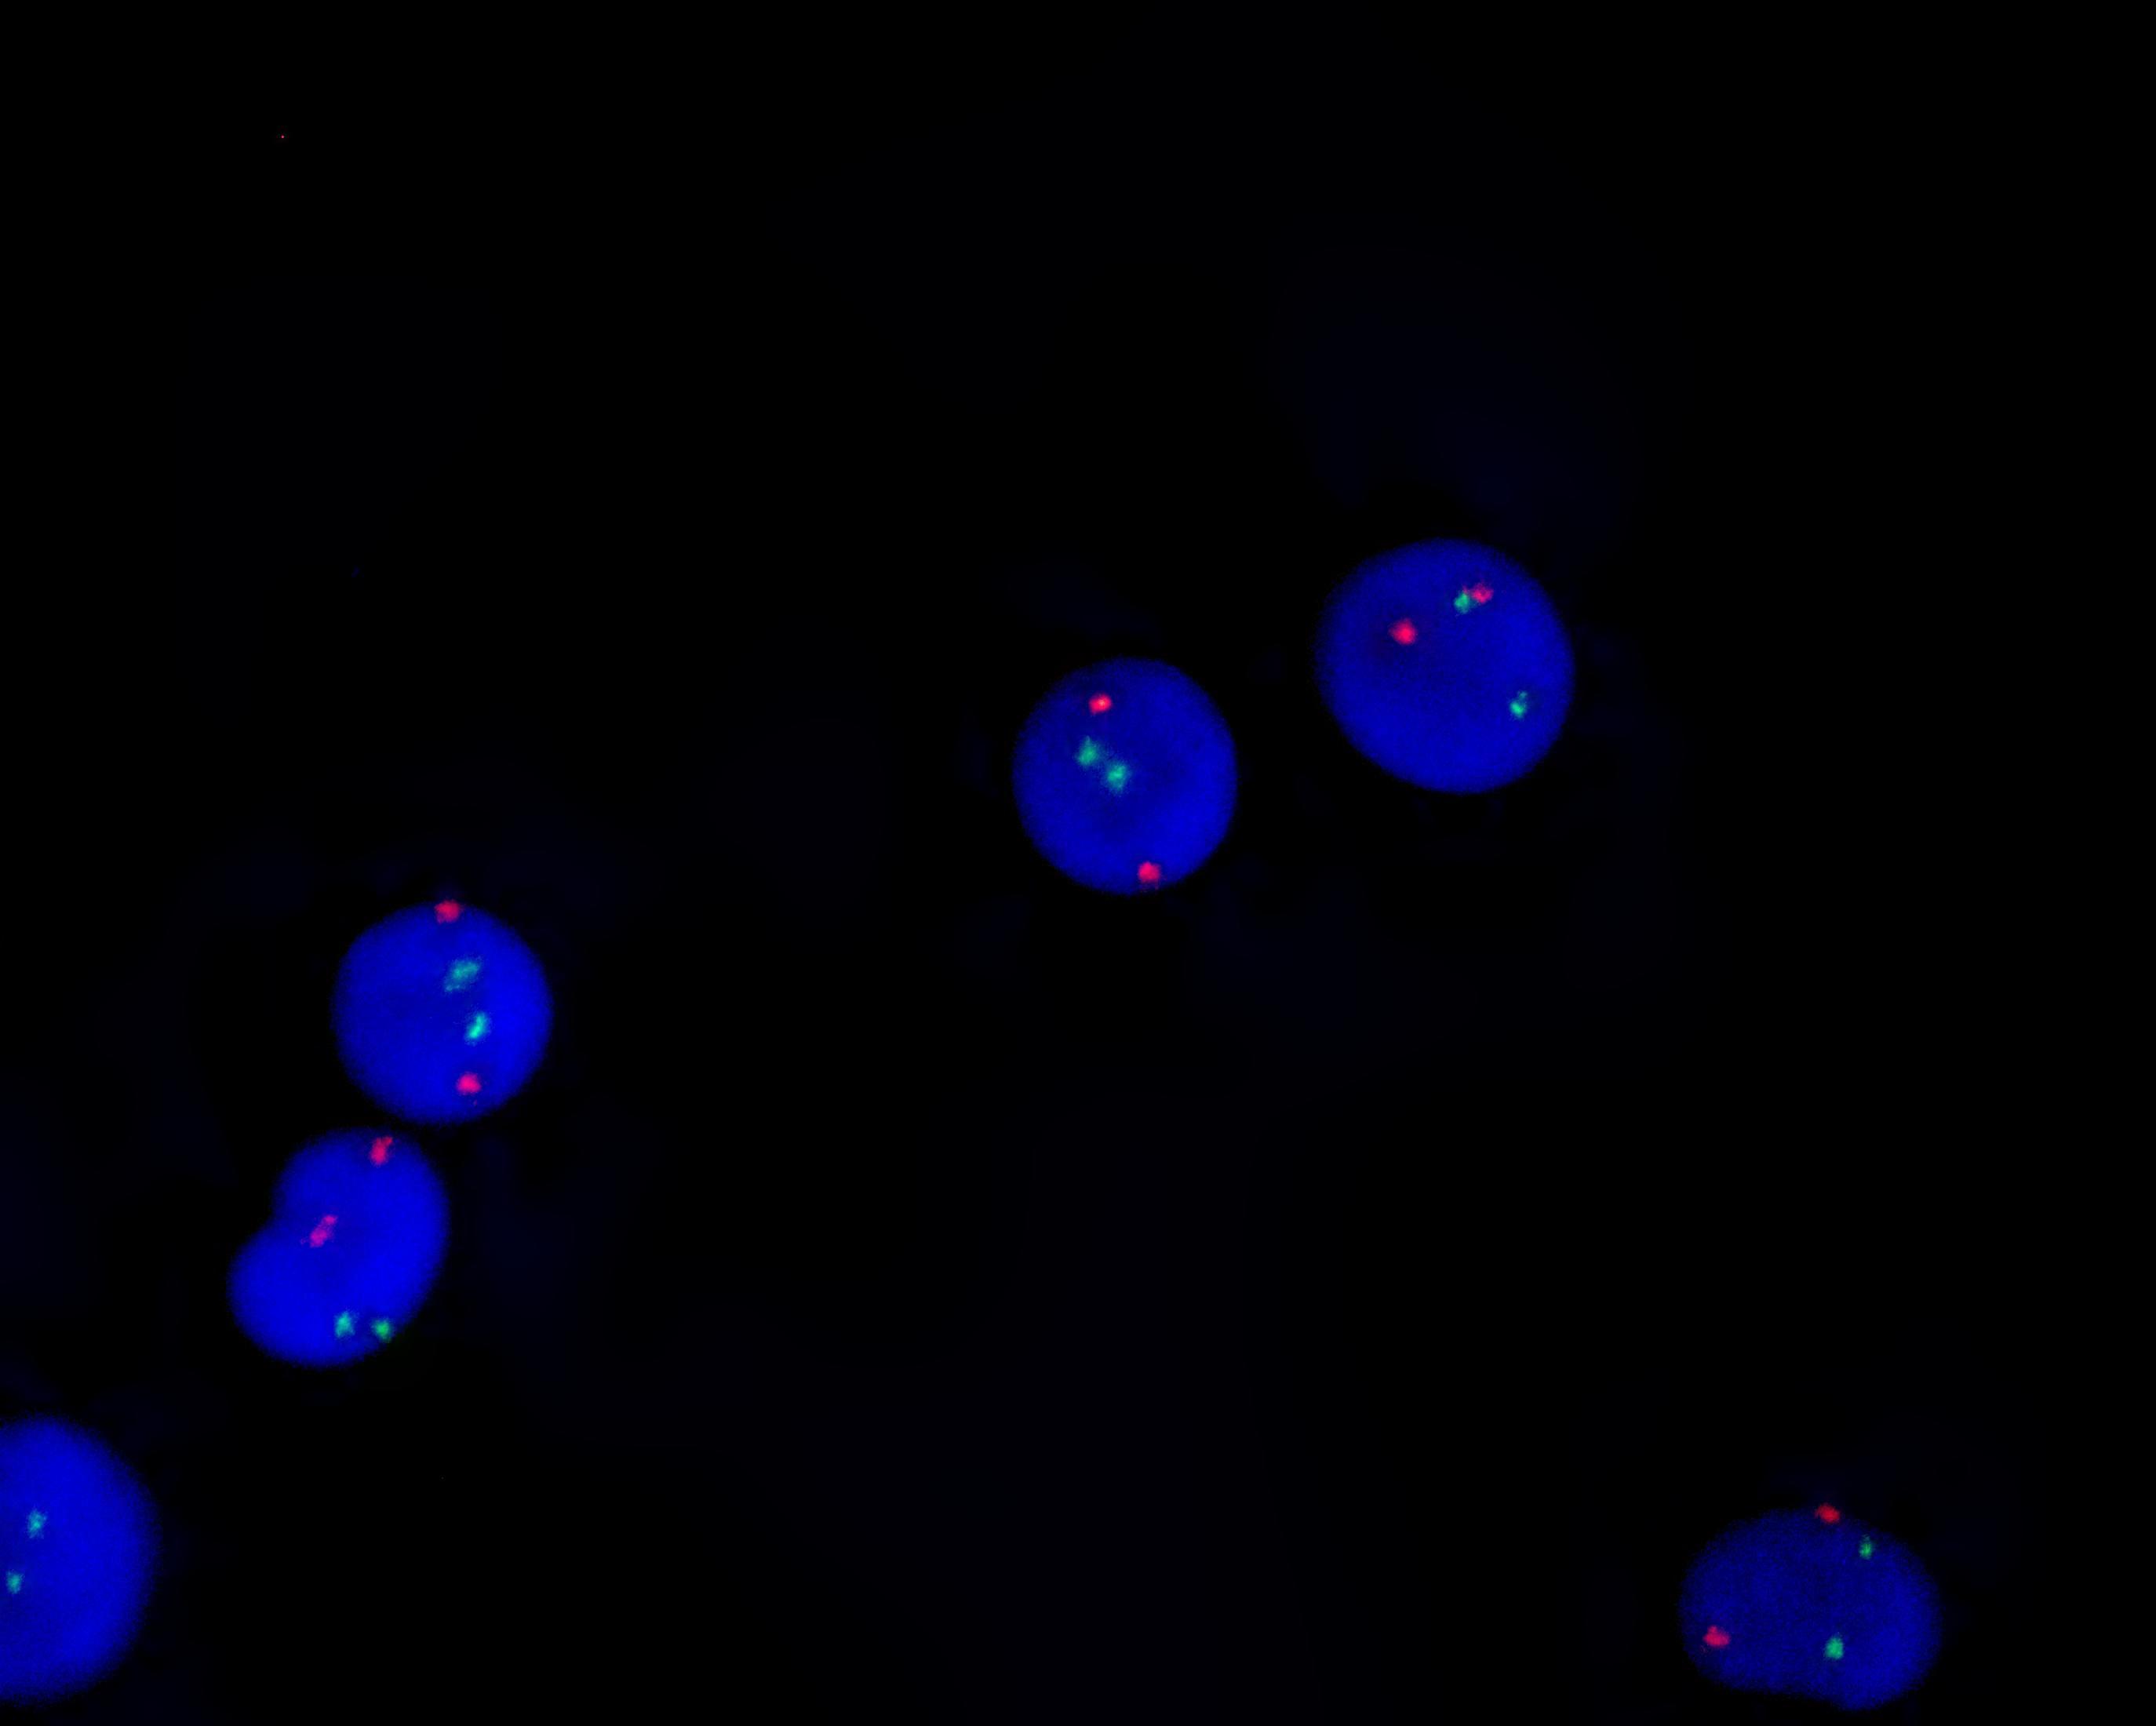

AML1/ETO gene fusion detection kit

AML1/ETO dual color probe

ETO gene (8q21.3-22.1) labeled as orange, with a length of 1000 kb; AML1 gene (21q22.11-22.12) labeled as green, with a length of 1100 kb.